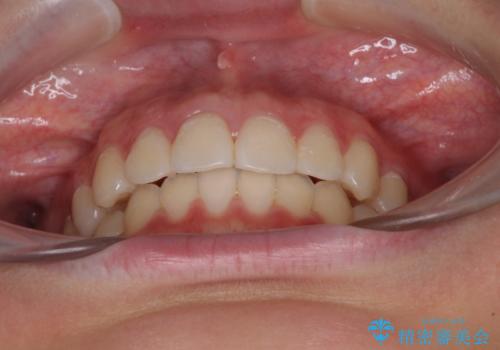

前歯のデコボコを改善 インビザライン矯正

- 口元のデコボコを気にして来院された患者様です。

前歯の捻れにより口元が閉じにくくなっていたため、歯列全体の側方への拡大と、歯と歯の間を少し削ってスペースを獲得することとしました。

ゴムかけをしっかりと行ってもらい、スッキリとした口元に仕上げることができました。